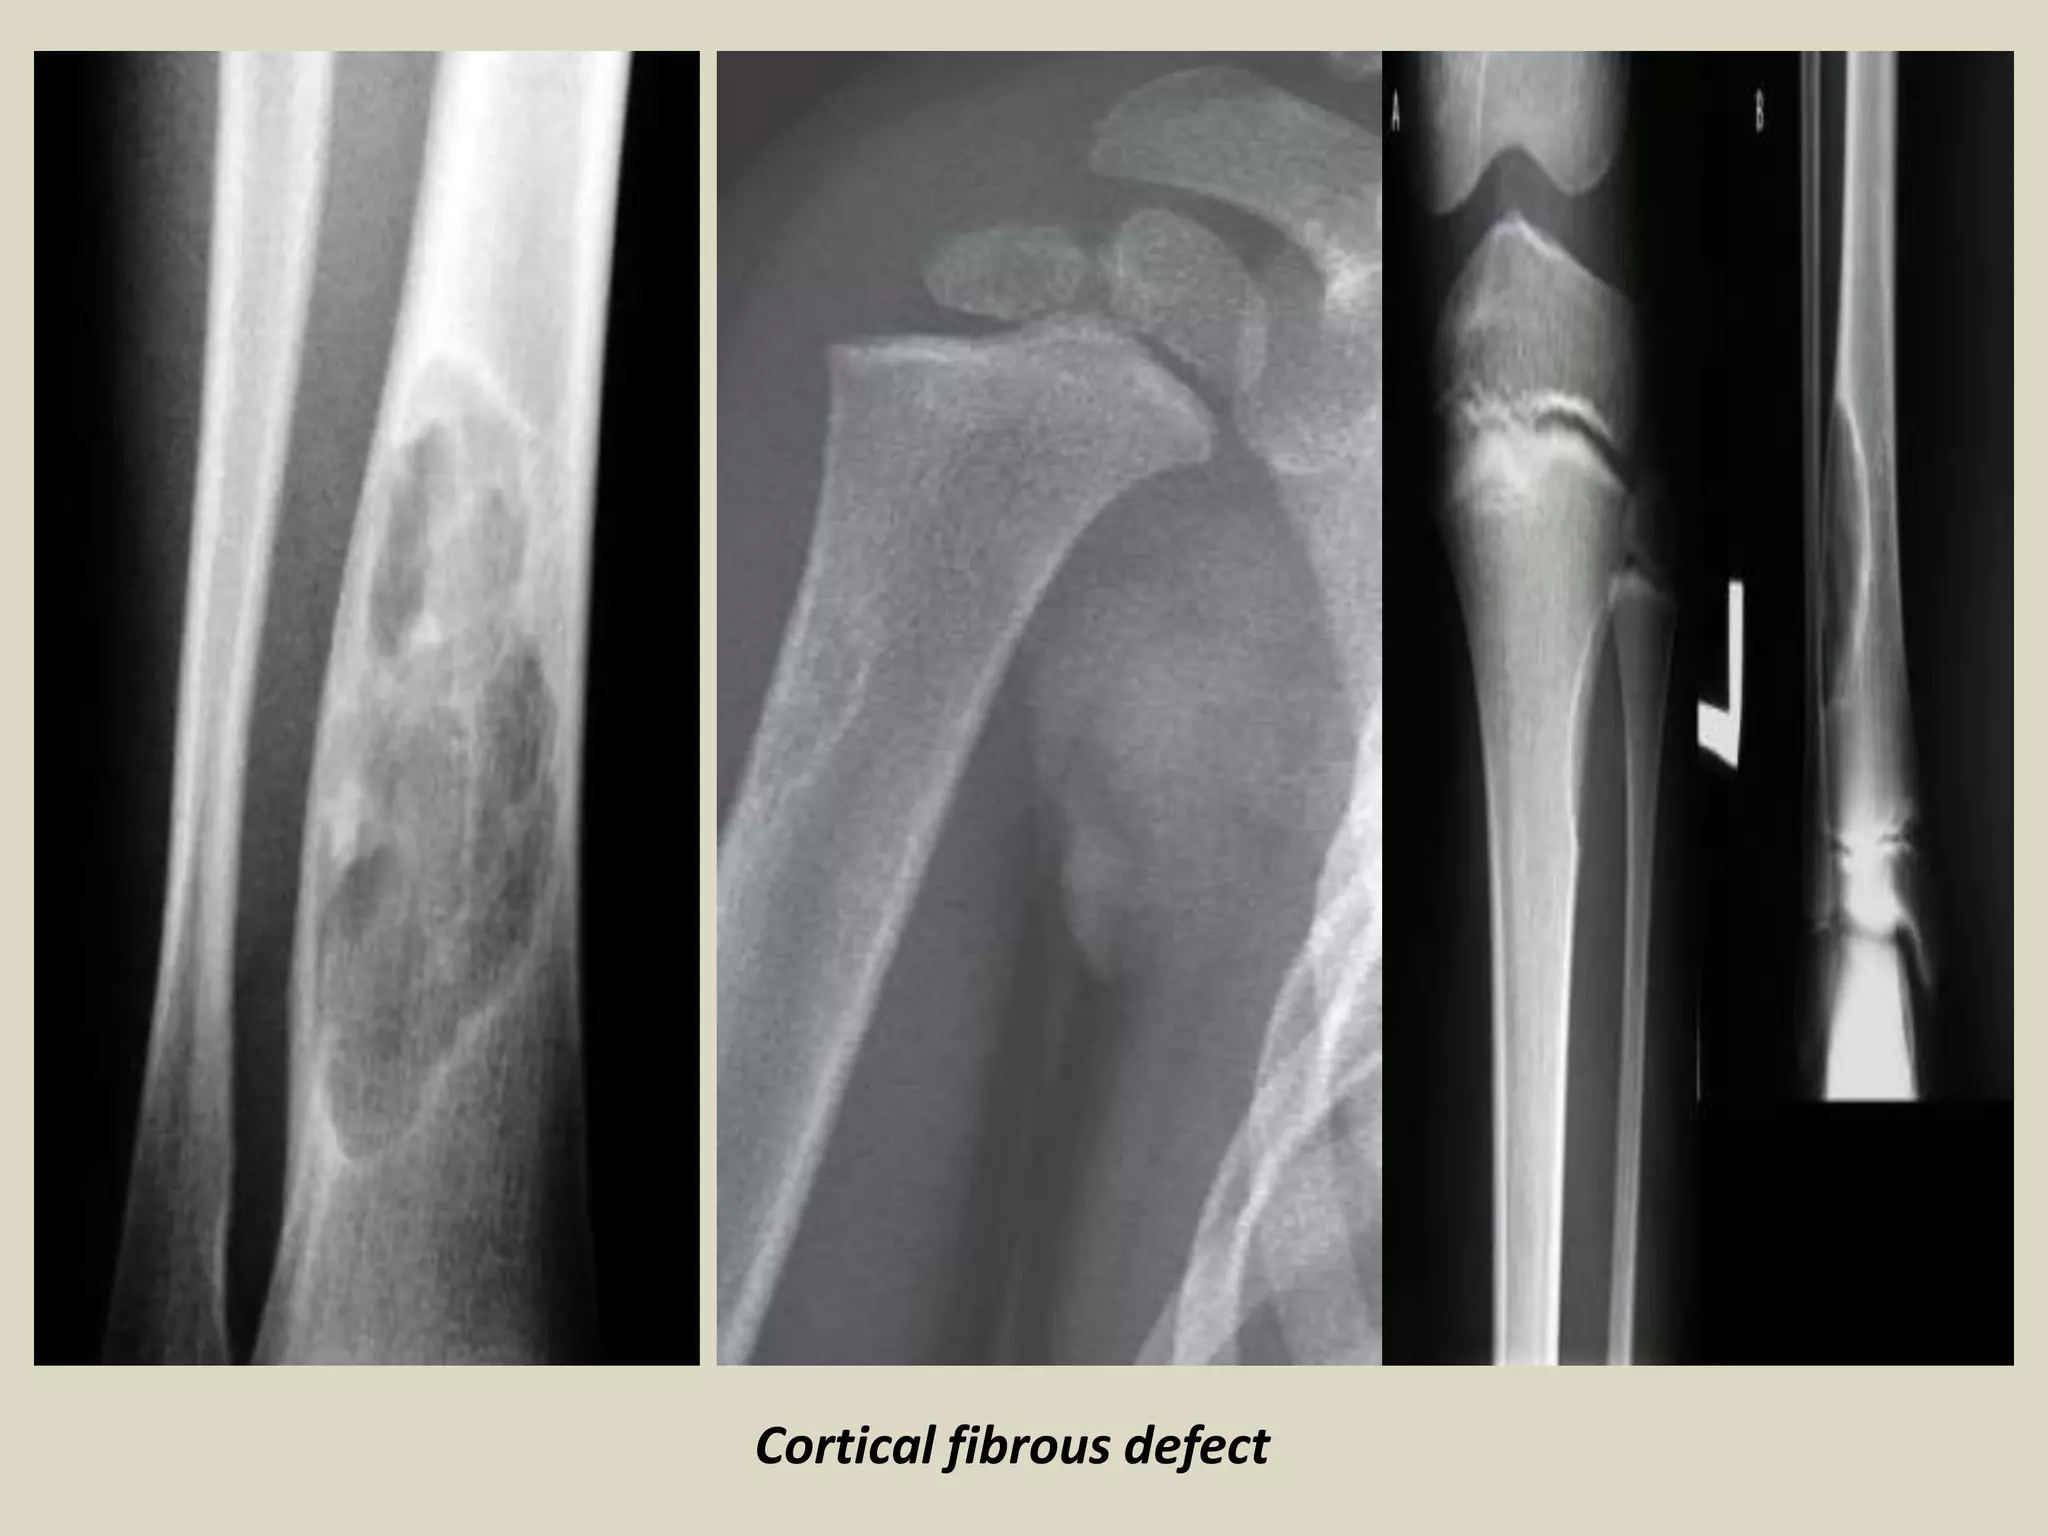

FIBROUS CORTICAL DEFECT/NON-OSSIFYING FIBROMA

- Benign lesion of bone composed of spindle-shaped fibroblasts, arranged in a storiform

pattern, with a variable admixture of multinucleated osteoclast-like giant cells.

- Epidemiology:

- Patient have ranged in age from 6 to 74 years old. 30-40% in children.

- An average age of 4 years 54% of boys and 22% of girls, had a lesion involving the

cortex, and most regressed spontaneously over a period of approximately 2.5 years.

Site of involvement:

- Approximately 40% of NOF occur in the long bones, with distal femur, distal and proximal

tibia most frequently involved.

- As many as 25% of cases involve the pelvic bone, in particular the ilium.

Clinical findings:

- Majority of NOF cases are asymptomatic, and are an incidental discovery on X-rays

performed for other reasons.

- Larger lesion may cause pain that is probably secondary to microfractures or obvious

pathologic fracture.

- Most pathologic fractures develop through lesions that involve more than 50% of the

diameter of the bone.

-The vast majority of NOF are single, although they are multiple in 8% of cases.

- Multiple NOF may be associated with syndromes such as neurofibromatosis.

Imaging:

- Eccentric, lytic lesions centered within the metaphyseal cortex and adjacent medullary cavity

- of long tubular bones.

- Well demarcated with sclerotic margins and frequently harbor internal trabeculation.

FIBROUS TUMORS

Cortical fibrous defect

Fibrous cortical defect.